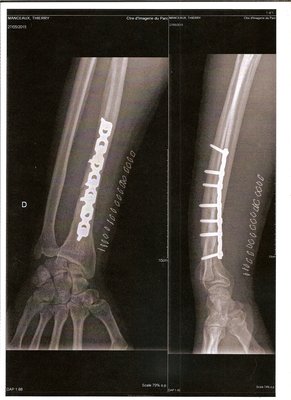

Ma fracture a nécessité un passage au bloc pour l’installation d'une plaque vissée, car la fracture était déplacée.

Petit cliché de la réparation, la plaque ressemble étrangement à ma chaine moto !